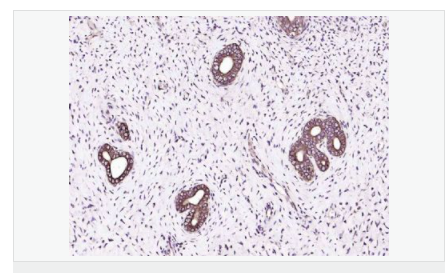

| 產(chǎn)品應(yīng)用 | WB=1:500-2000 ELISA=1:5000-10000 IP=1:20-100 IHC-P=1:100-500 IHC-F=1:100-500 IF=1:100-500 (石蠟切片需做抗原修復(fù)) not yet tested in other applications. optimal dilutions/concentrations should be determined by the end user. |

| 產(chǎn)品介紹 | The protein encoded by this gene is similar to insulin in function and structure and is a member of a family of proteins involved in mediating growth and development. The encoded protein is processed from a precursor, bound by a specific receptor, and secreted. Defects in this gene are a cause of insulin-like growth factor I deficiency. Several transcript variants encoding different isoforms have been found for this gene.[provided by RefSeq, Mar 2009] Function: The insulin-like growth factors, isolated from plasma, are structurally and functionally related to insulin but have a much higher growth-promoting activity. May be a physiological regulator of [1-14C]-2-deoxy-D-glucose (2DG) transport and glycogen synthesis in osteoblasts. Stimulates glucose transport in rat bone-derived osteoblastic (PyMS) cells and is effective at much lower concentrations than insulin, not only regarding glycogen and DNA synthesis but also with regard to enhancing glucose uptake. Subcellular Location: Secreted. DISEASE: Defects in IGF1 are the cause of insulin-like growth factor I deficiency (IGF1 deficiency) [MIM:608747]. IGF1 deficiency is an autosomal recessive disorder characterized by growth retardation, sensorineural deafness and mental retardation. Similarity: Belongs to the insulin family. SWISS: P05019 Gene ID: 3479 Database links: Entrez Gene: 3479 Human Omim: 147440 Human SwissProt: P05019 Human Unigene: 160562 Human Important Note: This product as supplied is intended for research use only, not for use in human, therapeutic or diagnostic applications. 胰島素樣生長(zhǎng)因子1(IGF-1)是一種生長(zhǎng)調(diào)節(jié)激素,由肝分泌并入血液循環(huán)的中性多肽,具有調(diào)節(jié)生長(zhǎng)和代謝、胰島素樣及促細(xì)胞分裂的活性,主要作用于成人。 |